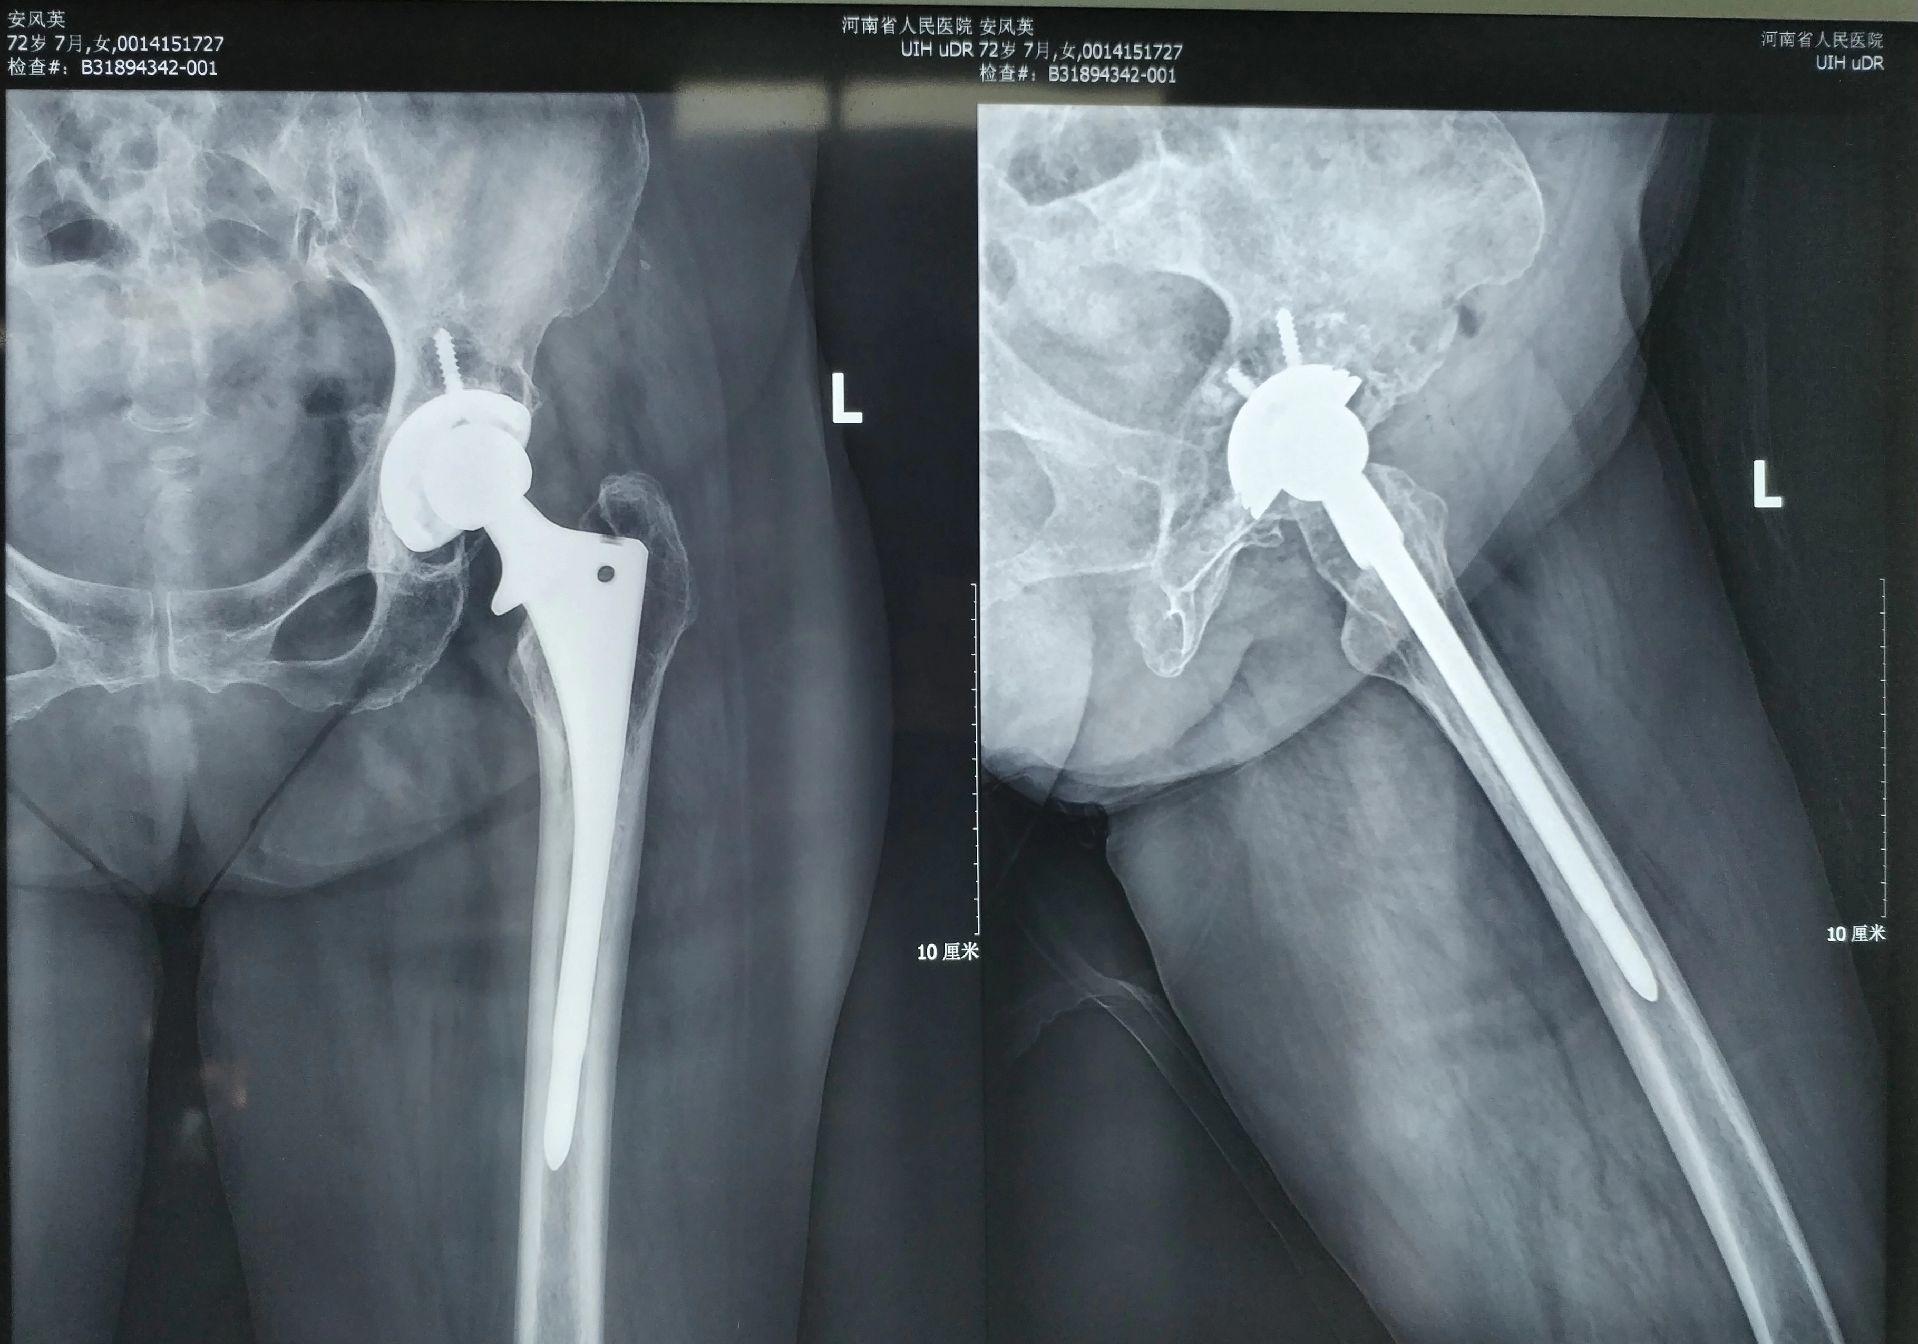

髋关节翻修。髋关节置换术后(外院)4年,磨损颗粒导致的无菌性松动,一期翻修,2天下床活动。磨损有好多因素,材质、体重、活动量等等。